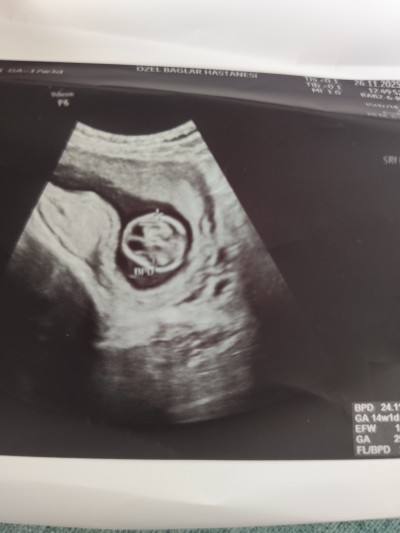

26 Kasım 2025 Hamilelik Dönemi Genel kategorisinde (119 puan) sordu

Merhaba arkadaşlar bugün ultrason girdim kontrole doktor bana bebeğin başında boşluk var öyle olup düzelme ihtimali var mı

Canım ilk kez duyuyorum ama bana sanki benekle ilgili değil de keseyle ilgili bir yorumda bulunmuş gibi geldi, post yukarı çıksın merakla bekliyorum